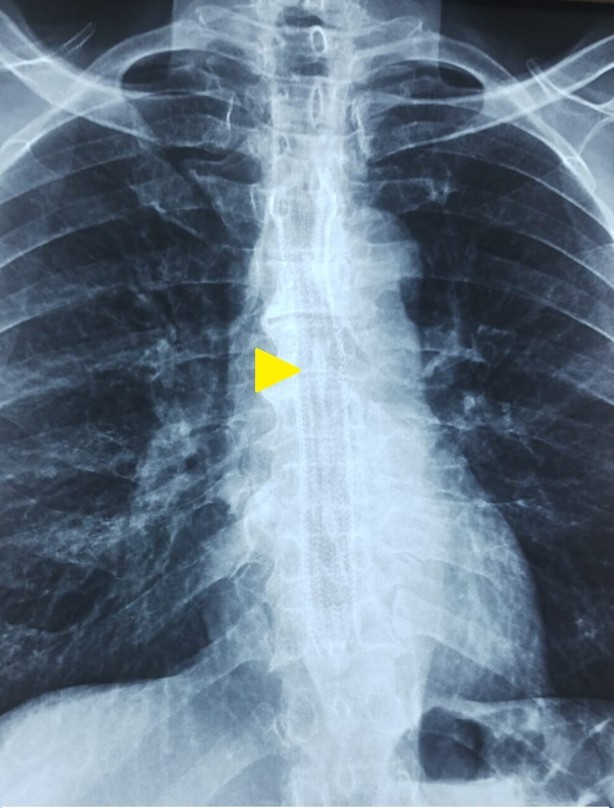

Due to unrespectable disease, the patient was planned for esophageal self-expanding metal stent placement (SEMS). Partially covered Esophageal SEMS of size 12 cm was placed starting from 19 to 31 cm, to sufficiently cover the trachea-esophageal fistula as well as the growth containing segment of esophagus (Figures 2 and 3). Post SEMS placement, the patient had relief in symptoms like dysphagia and recurrent cough.

Figure 3. X-ray image showing esophageal self expanding metal stent (E-SEMS) in situ (yellow arrow head).